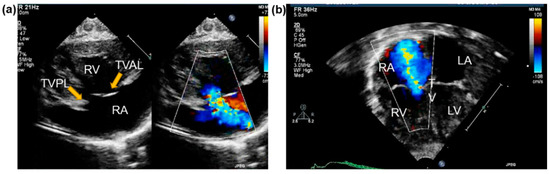

Two-Dimensional Imaging Modalities

Standard Echocardiography Imaging Windows